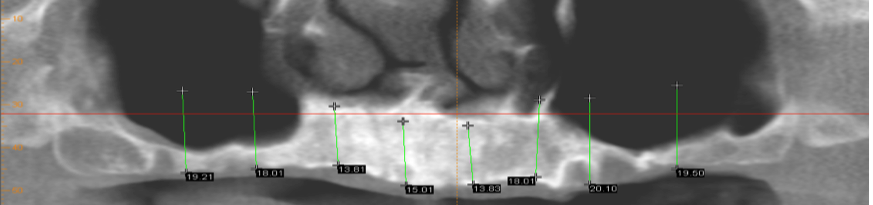

To provide an implant supported bridge for the top teeth when there is insufficient bone for implants, first we need to “grow” more bone. In the first image we have outlined the position and height of the proposed dental implants. There is insufficient bone to place these, so we first have to build the bone with a “sinus graft”.

To place the sinus graft we make small incisions in the gum and there is a thin membrane in the sinus that is lifted gently. A granular bone “scaffolding” is then placed. This surgical procedure is completed under sedation. Six months later the graft has converted to your bone (see image below).